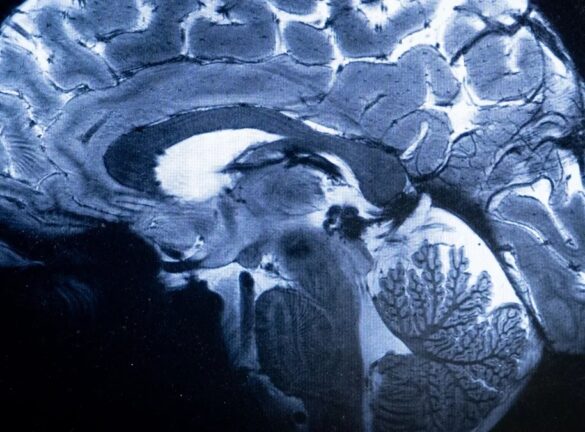

وأظهرت عمليات مسح التصوير بالرنين المغناطيسي لـ30 مريضا أدخلوا المستشفى بسبب “كوفيد 19” في وقت مبكر من الوباء قبل نشر اللقاحات، علامات على التهاب في جذع الدماغ، وهو جزء صغير لكنه بالغ الأهمية لأنه يتحكم بوظائف الجسم التي تدعم الحياة، مثل التنفس والنبض وحركة الدم.

وتشير عمليات المسح إلى أن الإصابات الشديدة بفيروس كورونا يمكن أن تثير رد فعل مناعيا يؤدي إلى التهاب جذع الدماغ، مما يسبب أعراضا يمكن أن تستمر لأشهر بعد خروج المرضى من المستشفى، وذلك حسب الدراسة المنشورة في صحيفة “برين” العلمية.

وسلطت الفحوصات الضوء على التشوهات المرتبطة بالالتهاب في أجزاء متعددة من جذع الدماغ، التي ظهرت بعد أسابيع من دخول المرضى إلى المستشفى، وكان الضرر لا يزال واضحا في عمليات المسح بعد أكثر من 6 أشهر.